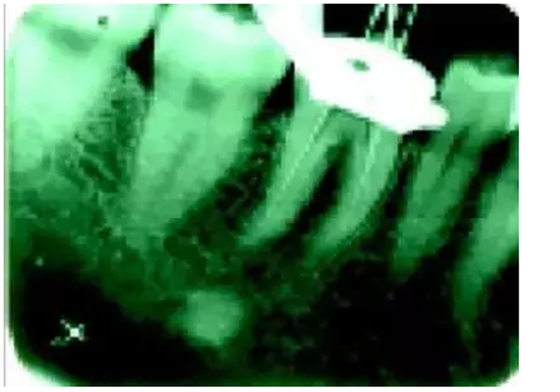

根管鈣化常見于外傷后的患牙,主要表現(xiàn)為X線片上根管系統(tǒng)的影像不清或消失。傳統(tǒng)的處理方法是使用根管銼、小號(hào)長柄球鉆(LN)、超聲器械或機(jī)用擴(kuò)孔鉆沿牙長軸方向切削牙本質(zhì),逐漸向根尖方向探查根管。對(duì)于根管較直的前牙,這種方法可以起到一定的作用。

對(duì)于后牙細(xì)小、彎曲的根管就很難疏通了。而且容易出現(xiàn)根管偏移、臺(tái)階、根管壁側(cè)穿等并發(fā)癥。

在手術(shù)顯微鏡高度放大下,較容易區(qū)分鈣化根管和正常牙本質(zhì)之間顏色和質(zhì)地的差別:顯微鏡下修復(fù)性和繼發(fā)性牙本質(zhì)的顏色較暗,呈黑色或褐色;鈣化度較高的組織一般顏色較正常牙本質(zhì)透明,正常牙本質(zhì)多呈淡黃褐色。這樣術(shù)者就可以在顯微鏡的引導(dǎo)下對(duì)切削部位有更精確的判斷,有效地減少根管偏移和根管壁穿孔的發(fā)生率。

術(shù)前應(yīng)首先根據(jù)X線片了解根管的鈣化程度、位置、根管的彎曲度、牙位等信息。開髓后,在顯鏡下仔細(xì)探察辨別鈣化根管和正常牙本質(zhì),避免破壞健康牙本質(zhì)結(jié)構(gòu),然后使用特殊的超聲工作尖(如ET40、ET20等)可以較容易地疏通鈣化根管。

有時(shí)超聲預(yù)備根管可能會(huì)深達(dá)距根尖幾個(gè)毫米。治療過程中需配合使用根管銼進(jìn)行探查并拍X線片檢查,防止器械偏離根管長軸,如此反復(fù)操作直到疏通根管并到達(dá)根尖。需要注意的是由于X線片僅能反映二維重疊影像,當(dāng)切削方向向頰側(cè)或舌側(cè)偏移時(shí),不易診斷。為了軟化鈣化組織,術(shù)中推薦使用17%EDTA進(jìn)行根管沖洗。